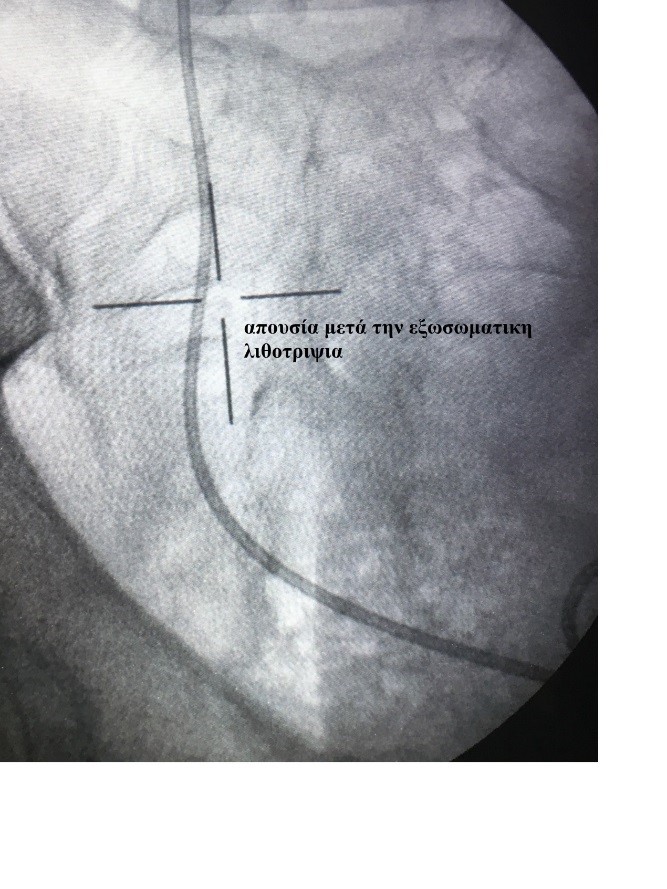

- Εξωσωματική λιθοτριψία Λίθοι μέχρι 1,5 εκατοστό είναι υποψήφιοι για εξωσωματική λιθοτριψία, μία μέθοδο ανώδυνη χωρίς την ανάγκη αναισθησίας και μη επεμβατική με καταγεγραμμένα μεγάλα ποσοστά θραύσης των λίθων. Η στόχευση των λίθων γίνεται με ακτινοσκόπηση ή με την βοήθεια υπερήχων.

|